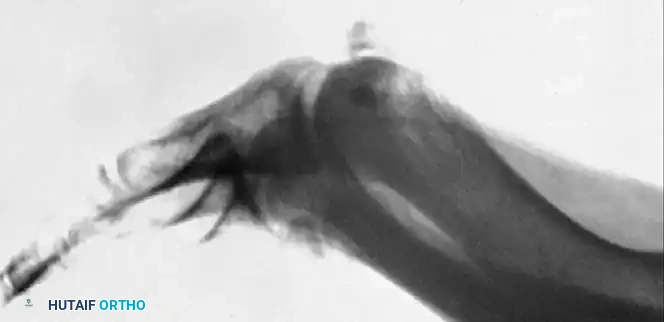

Fig. 78-96 Tibial sesamoid is profiled on the medial oblique view. A, Position of the foot. B, Sesamoid in profile.